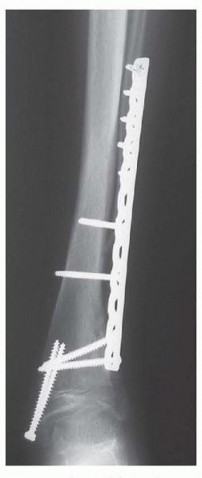

## For varus deformities, an opening wedge is created along the same line. Once the osteotomy is made, the osteotomy site is distracted using a lamina spreader to the preplanned distance to correct the deformity (TECH FIG 4A-C).

## It is then held open by a wedge-shaped tricortical iliac crest graft or simply stabilized with a medial plate and screws (TECH FIG 4D-H), beginning with a screw passed from medial to lateral across the osteotomy site.

TECH FIG 4 • A. Position of the two Crego elevators used to protect the soft tissues during the oblique osteotomy. An oscillating saw is used to create the oblique osteotomy. Fluoroscopy is used to confirm the angulation of the cut as well as to ensure that the lateral cortex remains intact. B. A large osteotome is placed into the osteotomy site and used to open the osteotomy. C. A laminar spreader is used to hold open the osteotomy site. D. The amount of medial opening needed for deformity correction is verified by measuring the medial opening in millimeters. (continued)

P.563

## TECH FIG 4 • (continued) E. A bicortical 3.5-mm screw (cortical) is inserted from the proximal to distal fragments to hold the osteotomy site open, allowing for removal of the laminar spreader. F. A 3.5-mm small fragment dynamic compression plate is contoured to the medial aspect of the distal tibia. G. The plate is secured to the distal tibia with 3.5-mm cortical bone screws. H. Intraoperative AP radiograph showing opening wedge osteotomy with internal fixation.